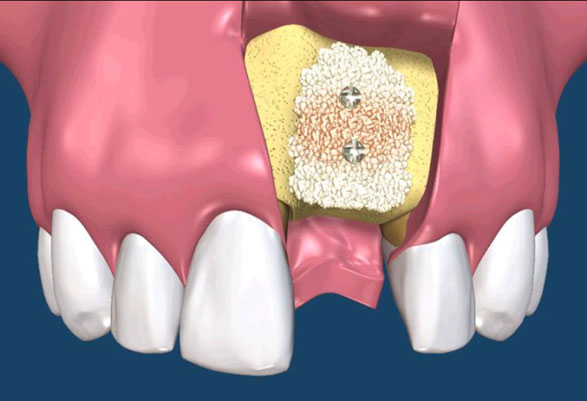

骨粉合併再生膜

在 GTR 及 GBR 技術中所使用的阻隔膜是用來將缺損的區域分開成兩個隔間。 GTR 技術的目的是再生完全俱功能的牙周膜,包含新的牙骨質、牙周韌帶(PDL)及新骨。GBR 技術的目的是再生新骨,對此,細胞從下層的骨組織需要分佈至缺損處。(圖09-12)